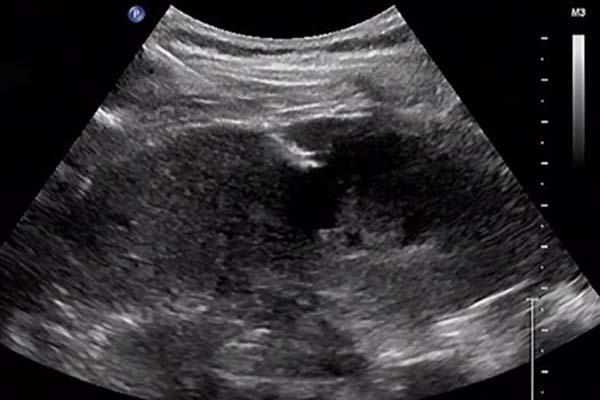

术前,医护团队向患者详细说明穿刺的意义、必要性及可能的风险与并发症。患者虽有顾虑,但基于对医院技术实力与设备条件的信任,最终欣然接受治疗方案。8月13日13时,患者在肾内科翟莎娜医师陪同下进入微创手术室。超声医学科主任孙心平对移植肾进行细致超声评估,与肾内科主任余永武充分沟通后,共同确定最佳穿刺部位。在孙心平实时超声引导下,余永武精准操作,顺利完成穿刺活检,取材满意,获取2条肾组织标本。术中患者生命体征平稳,无明显不适;术后一般情况良好,血压稳定,无血尿、穿刺部位疼痛等不适。

在余永武带领下,清华大学附属垂杨柳医院肾内科自2018年起已开展肾穿刺活检近300例。该技术采用全自动肾穿刺活检针,在B超实时引导下操作,能清晰观察穿刺针进入肾脏的全过程,并可根据需要随时调整角度,具有安全性高、并发症少、取材成功率高、操作便捷、无放射性损伤、患者易接受等优势,已成为诊断肾功能损害的常规检查手段。